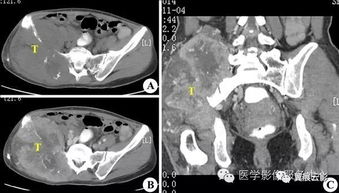

解析:在诊断骨肿瘤时,MRI具有较高的诊断价值。MRI可以清晰地显示肿瘤的形态、大小、边界以及与周围组织的关系,有助于判断肿瘤的性质和分期。此外,MRI还可以观察到肿瘤对周围血管、神经等结构的侵犯情况,为临床治疗提供重要依据。